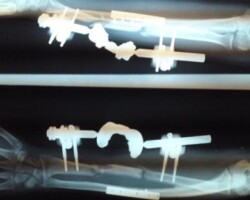

Αγγειούμενη περόνη

Άντρας 21 ετών υπέστη διπολικό κάταγμα της κερκίδας και κάταγμα της ωλένης, που αντιμετωπίστηκε σε περιφεριακό νοσοκομείο. 9 μήνες μετά διαπιστώθηκε ψευδάρθρωση της κερκίδας με οστικό απόλυμα 6,5 εκ. Αντιμετωπίστηκε με τη χρήση αγγειούμενης περόνης, η οποία γεφύρωσε το οστικό έλλειμμα της κερκίδας.